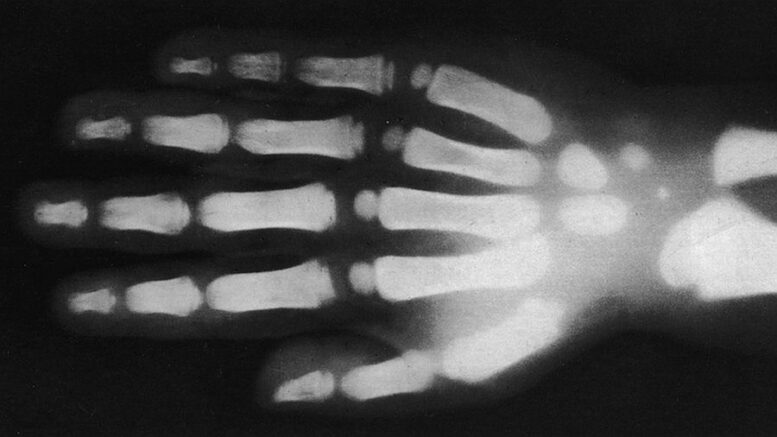

The X-ray files: Also sounding a bit like science fiction was German physician Wilhelm Röntgen’s ability to see through skin and metal using electromagnetic radiation, which went public on Jan. 5, 1896.